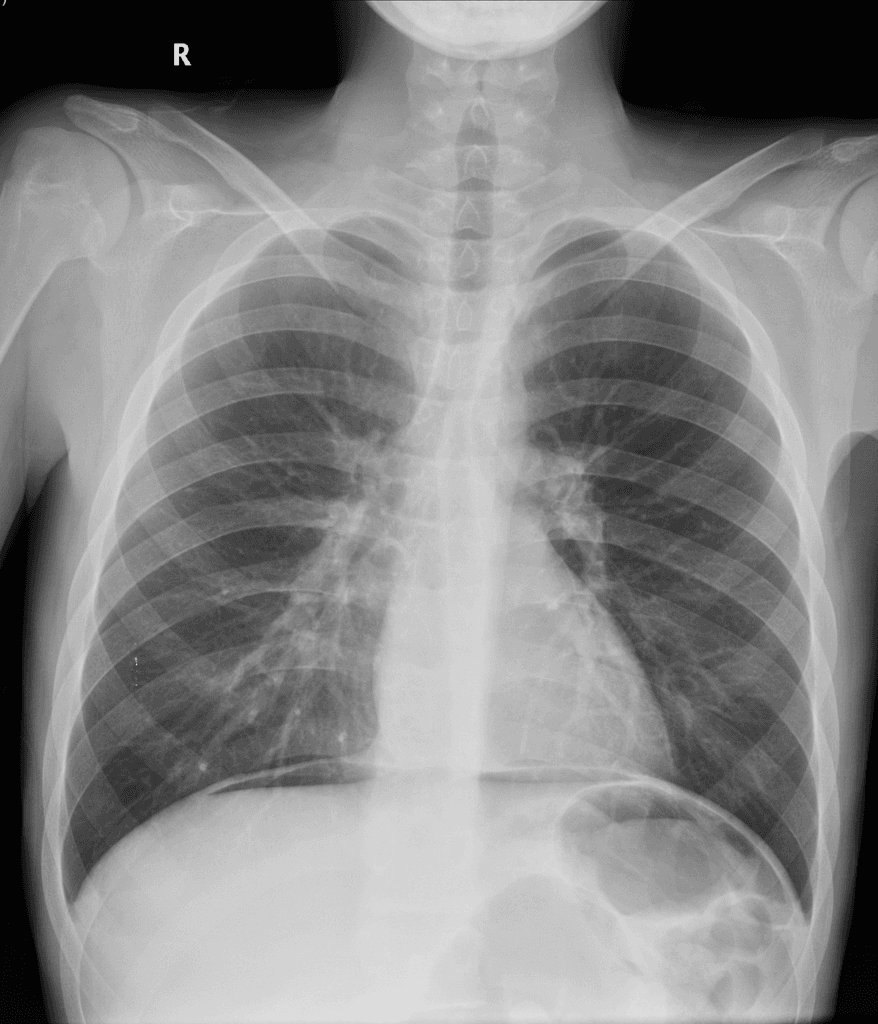

Có các dấu hiệu viêm hoạt động ảnh hưởng đến đoạn cuối ruột non và đoạn đầu ruột già: dày thành ruột (mural thickening), phù (edema), hạn chế khuếch tán (restricted diffusion) và tăng quang sau tiêm thuốc đối quang ở đoạn cuối 30 cm của ruột non và manh tràng (cecum). Mô hình tăng quang có dạng mục tiêu (targetoid), với tăng quang ở lớp niêm mạc và thanh mạc. Trong đoạn ruột bất thường này, có các đoạn ngắn không bị tổn thương, tại đó thấy các túi nhỏ ở bờ đối mạc tràng (anti-mesenteric border sacculation). Phía trên đoạn bệnh lý, có hiện tượng giãn nhẹ. Ngoài ra, ghi nhận sự tăng sinh mỡ ở vùng hạ vị phải, làm tách biệt các quai ruột bị bệnh khỏi các quai ruột còn lại trong ổ bụng. Có thể thấy hình ảnh hình thành đường rò giữa hồi tràng và manh tràng liền kề. Có nhiều hạch bạch huyết viêm trong mạc treo ruột non. Không thấy hình ảnh (no evidence of) tổn thương ở ruột non đoạn gần hoặc các đoạn khác của đại tràng. Các đoạn ruột viêm có nhu động giảm. Không thấy hình ảnh dịch tự do hoặc ổ dịch trong ổ bụng hay tiểu khung.

Hình ảnh cho thấy các đặc điểm điển hình của bệnh viêm hoạt động, bao gồm dày thành ruột và phù, tăng quang dạng lớp (layering enhancement), hạn chế khuếch tán, mỡ bao quanh (fat wrapping), và tạo túi giả dọc theo bờ đối mạc tràng. Ngoài ra, có bằng chứng của bệnh lý xuyên thành (transmural disease) với hình thành đường rò giữa hồi tràng và manh tràng.